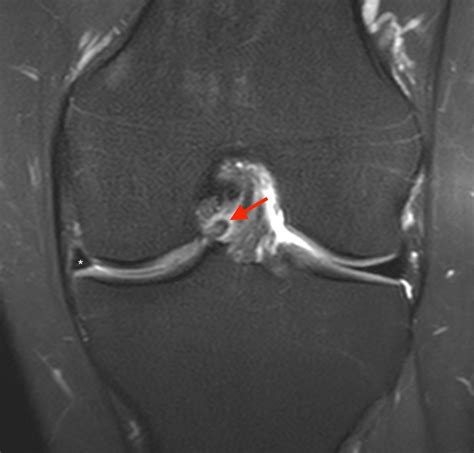

• Magnetic Resonance Imaging (MRI) to provide detailed images of the meniscus and surrounding structures. MRI is particularly useful in identifying the location and extent of the tear.

In some cases, an arthroscopy may be performed to directly visualize the meniscus and confirm the diagnosis. This minimally invasive procedure involves inserting a small camera into the knee joint through a tiny incision.